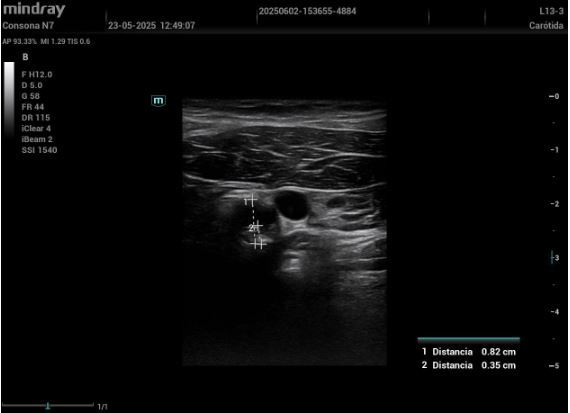

De esta forma, comenzamos a utilizar la ecografía no solo como herramienta diagnóstica, sino también como instrumento de concienciación visual. Así, mostramos en directo al paciente sus placas de ateroma en carótidas o femorales, o la hiperecogenicidad hepática fruto de su esteatosis. Al ver su daño, muchos cambian de actitud. Frases como «¿esto está dentro de mí, doctora?» se repiten, y suelen ir seguidas de decisiones reales. Ese momento es mágico. La negación se rompe. La conciencia se enciende. El cambio empieza. Tras ver sus imágenes, pacientes que no tomaban tratamiento empezaron a hacerlo. Fumadores empedernidos pidieron ayuda. Personas que decían «ya adelgazaré» empezaron a perder peso. Todo, porque lo vieron.